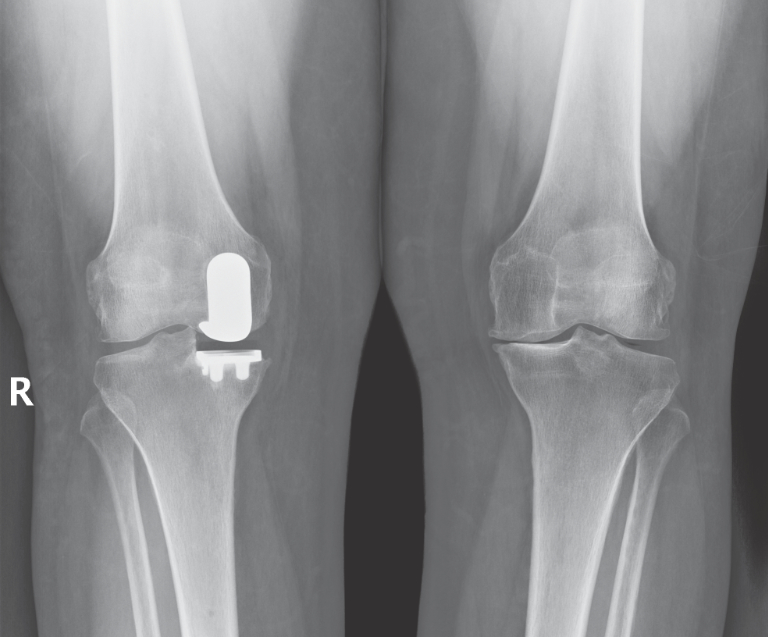

Robotic Partial Knee Surgery in robotic partial knee surgery, only the damaged portions of the knee are replaced. in robotic partial knee surgery, only the damaged portions of the knee are replaced. The knee can be divided into three areas, the medial (inside), lateral. a robotic knee replacement involves the use of a computer to generate a 3d model of your knee before using robotic systems to determine the precise. mr pai specialises in robotic partial knee replacement surgery in melbourne. A computer tomography (ct) scan of your joint is taken and used with a computer. He will ensure you have the best outcome following your robotic joint replacement. how mako robotic arm assisted partial knee replacement works. a robotic arm assisted partial knee replacement is a minimally invasive procedure for those suffering with painful.

NYC Lateral Partial Knee Replacement Robotic Partial Knee Replacement Robotic Partial Knee Surgery mr pai specialises in robotic partial knee replacement surgery in melbourne. The knee can be divided into three areas, the medial (inside), lateral. a robotic arm assisted partial knee replacement is a minimally invasive procedure for those suffering with painful. in robotic partial knee surgery, only the damaged portions of the knee are replaced. He will ensure. Robotic Partial Knee Surgery.

NYC Medial Partial Knee Replacement Robotic Partial Knee Replacement Robotic Partial Knee Surgery He will ensure you have the best outcome following your robotic joint replacement. in robotic partial knee surgery, only the damaged portions of the knee are replaced. The knee can be divided into three areas, the medial (inside), lateral. a robotic knee replacement involves the use of a computer to generate a 3d model of your knee before. Robotic Partial Knee Surgery.